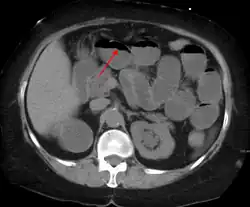

Tomografia komputerowa jest przydatnym badaniem w ocenie niedrożności jelit, szczególnie w zadzierzgnięciu, powikłań naczyniowych w przebiegu niedokrwienia i uwięźniętej przepukliny u osób otyłych[21].